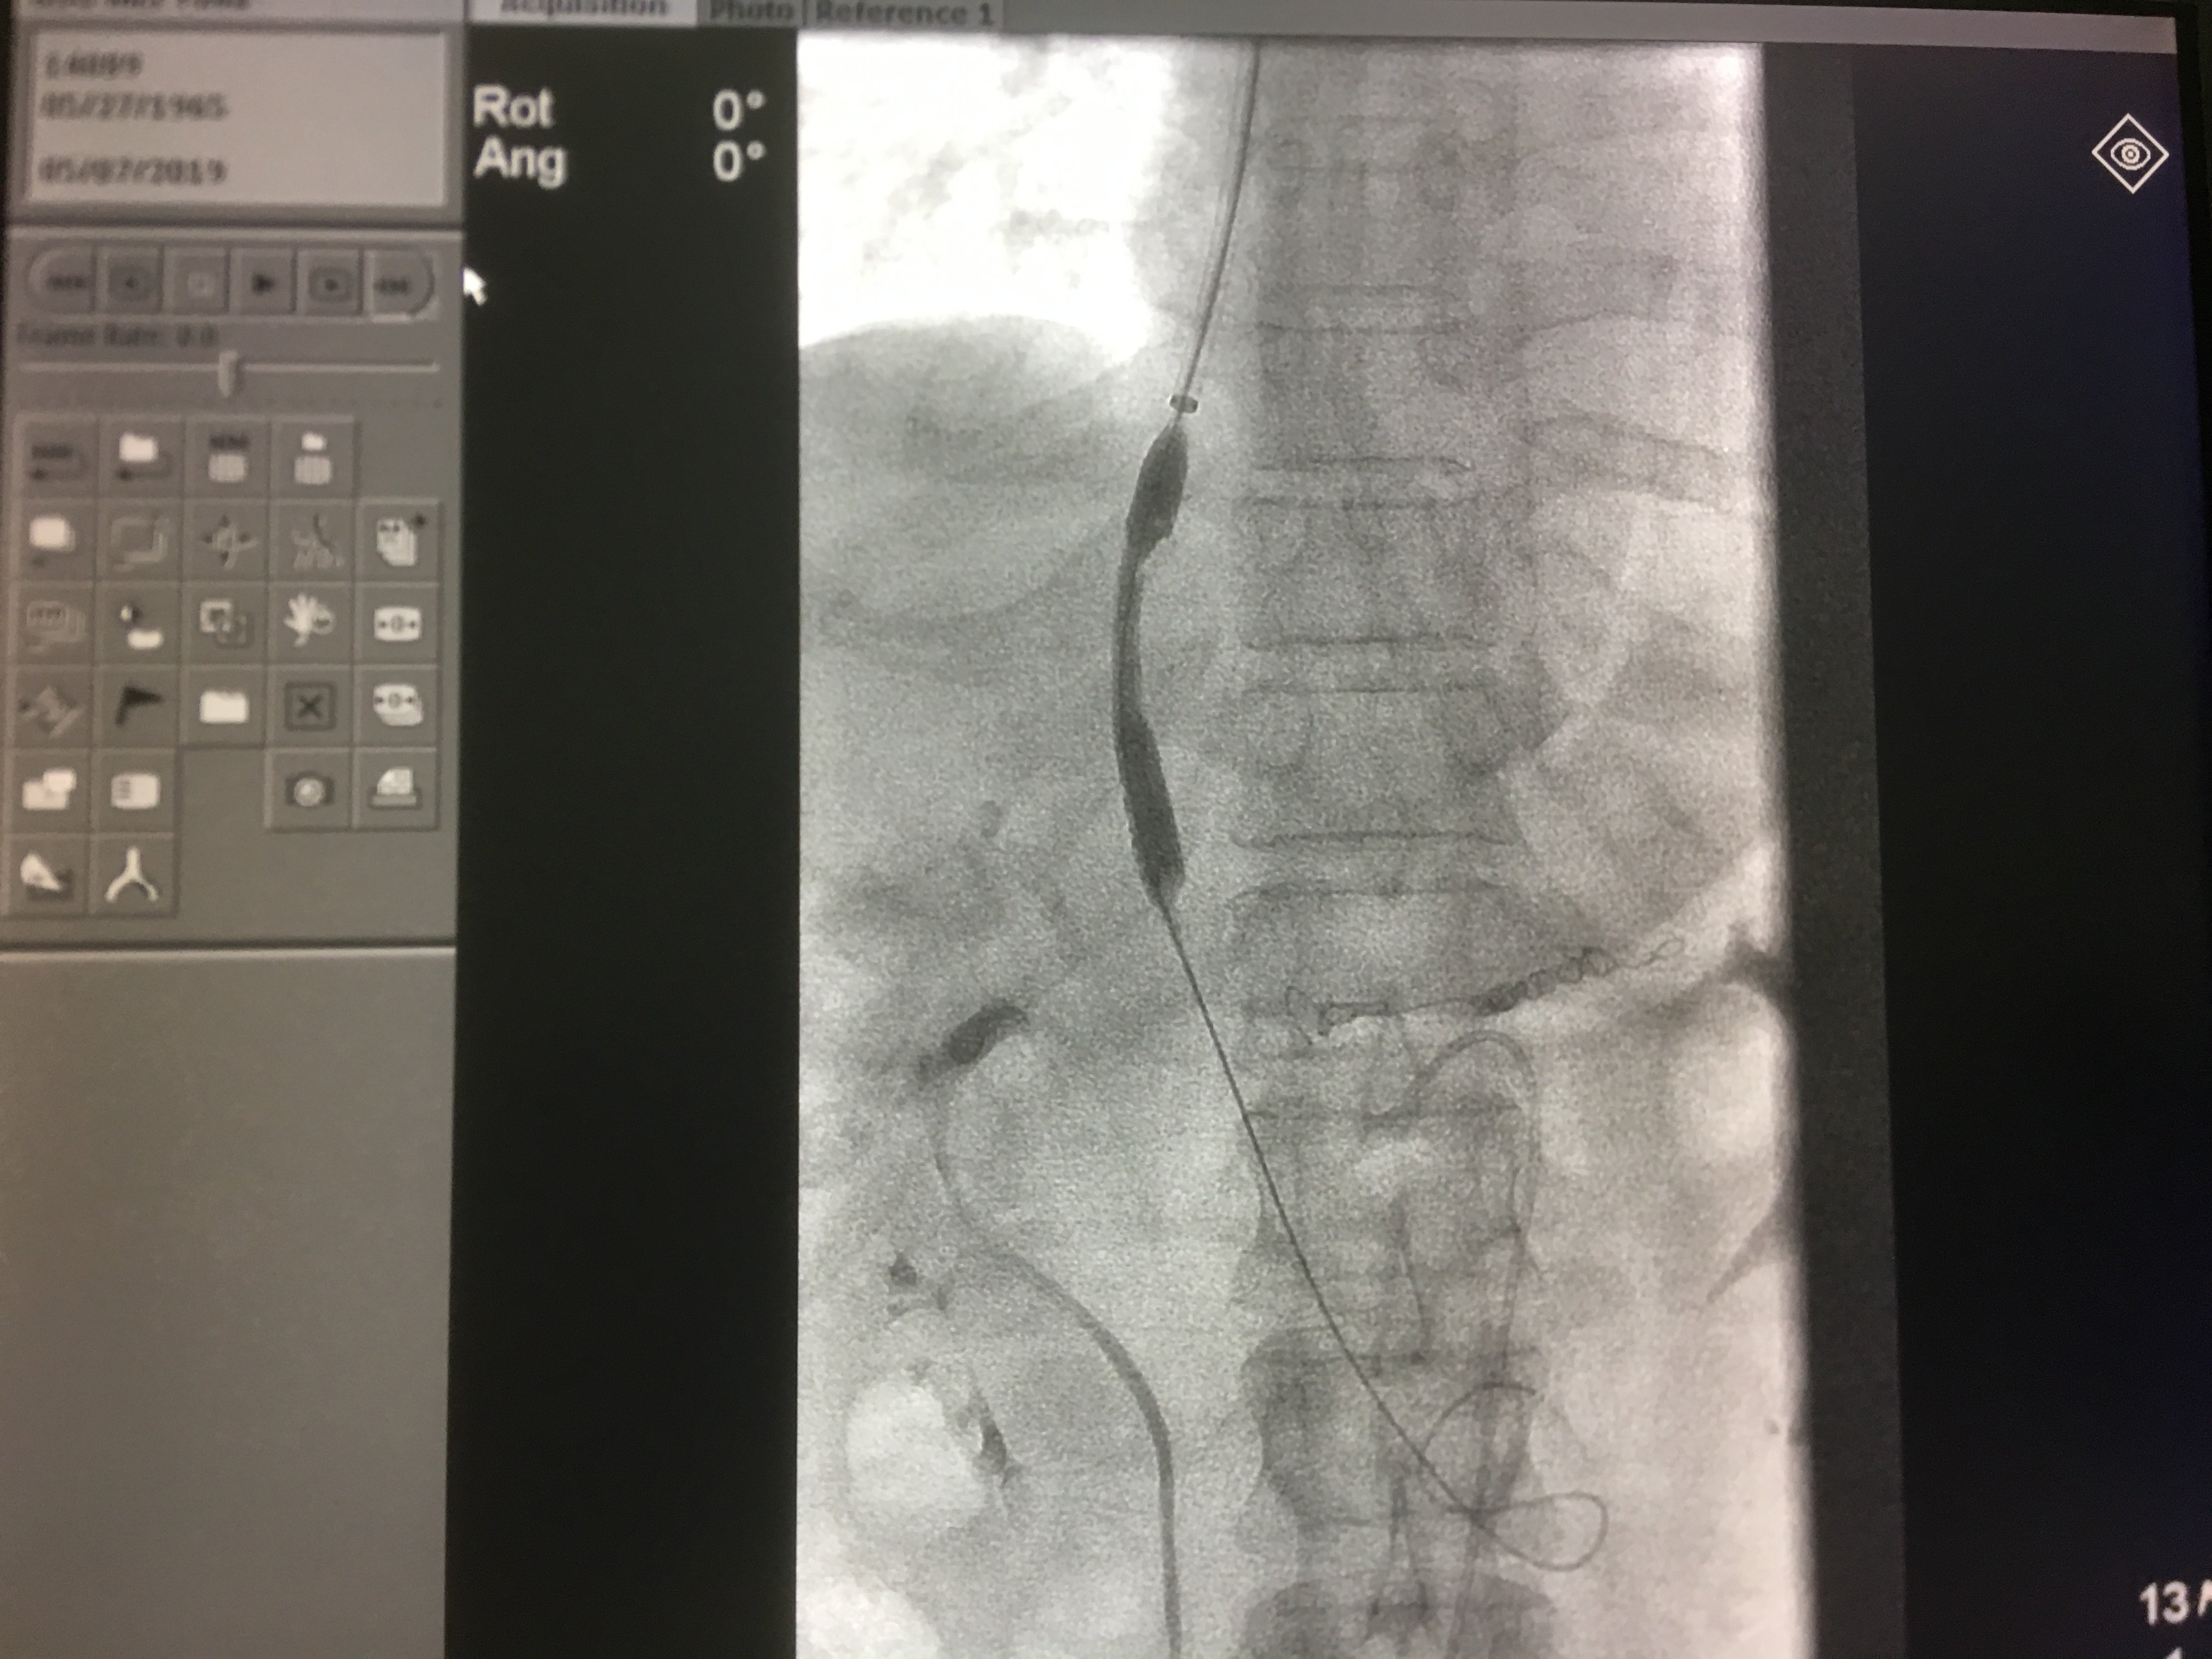

调整角度穿刺成功后进行直接门静脉造影,测门静脉压力。